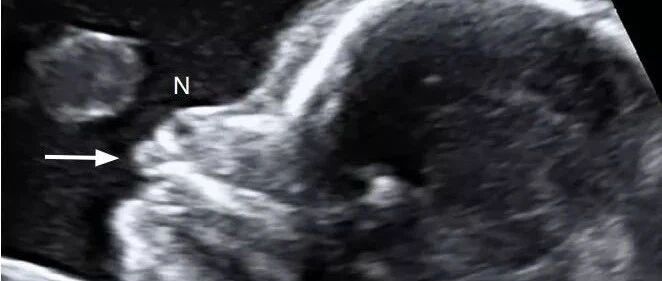

「 小儿颅脑超声」之新生儿脑实质出血 丁香园超声时间 · 公众号 · 医学 · 1 年前 · |